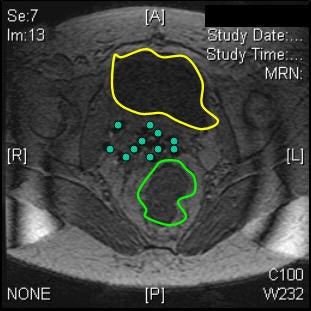

| Interstitial reconstruction, MR (above) versus CT (below). Patient must be imaged with legs down. |

The patients' legs were then brought down and they were reimaged for the CT simulation. "We learned that it was very important to image with the legs down. There was substantial movement with the legs down. But once we figured that out, we were able to perfectly reconstruct the images so that the catheters lined up on MR," Viswanathan said.

"We then have the radiologist look at the series of MR images obtained and reposition the obturator so that the needles were directed at the tumor," Viswanathan explained. "We then do the insertion on real-time MR guidance. It doesn't mean that as we are putting in the needles, we are seeing them go in. It does mean that we put the needles in, scan the patient in ... axial or sagittal planes, look at where the needle is, and readjust. Then we get final MR imaging after all the needles have been inserted and we're happy with our tumor volume."